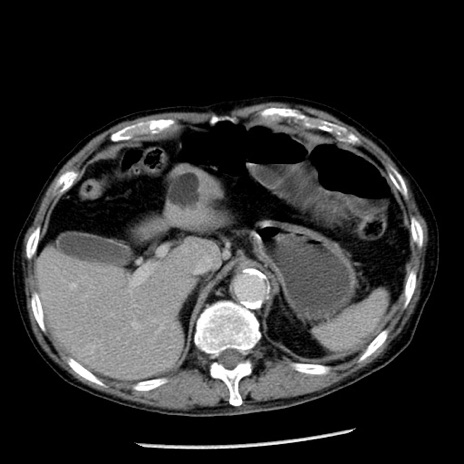

症例26(横断像)

【症例】80歳代男性

【主訴】嘔吐

【現病歴】昨晩2回嘔吐あり、今朝になっても嘔吐あり。来院。

【既往歴】胃潰瘍

【身体所見】意識清明、BT 37.6℃、BP 166/95mmHg、HR 100bpm、SpO2 97%、腹部:平坦・軟、腸蠕動音聴取良好、圧痛なし。

【データ】WBC 21900、CRP 1.46